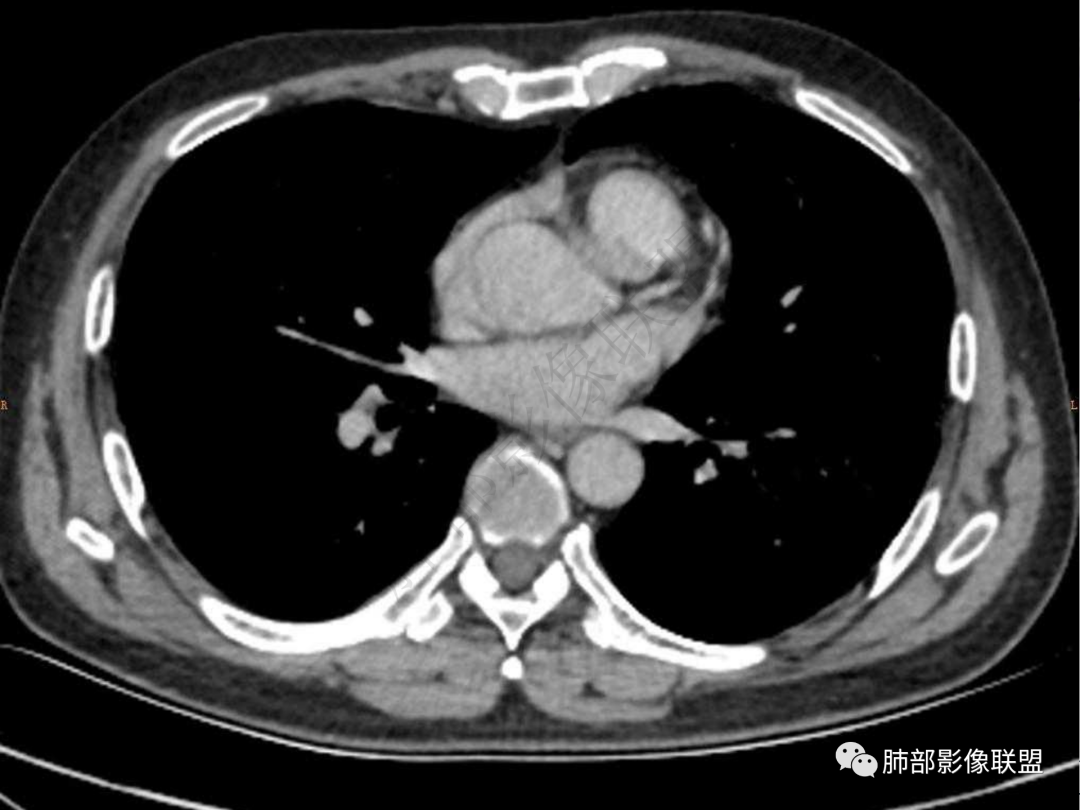

4.实性部分不均匀环形强化并显示一小范围低密度坏死区或空洞。较之肺窗,整体纵隔窗范围较小,提示病灶并不十分密实。抑或为不同时段图像。

5.双肺门及纵隔未见增大淋巴结。未见胸腔积液。

六:增强扫描:

肺脓肿:环形强化,强化较显著。如出现明显囊壁样强化甚至边缘“憩室”样突出,高度支持肺脓肿。